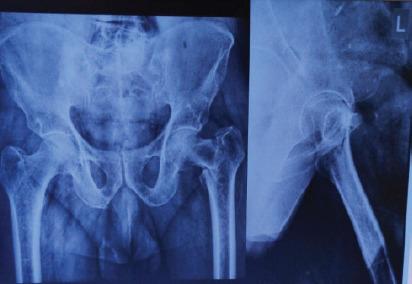

Intertrochanteric femur fractures are among the most common injuries in the elderly population and represent a major public health issue. Treatment aims to achieve stable fixation that allows early mobilization and minimizes complications. The choice of implant plays a critical role in clinical outcomes, particularly in unstable fracture patterns.

股骨粗隆间骨折是老年人群中最常见的损伤之一,是一个重大的公共卫生问题。治疗的目标是实现稳定的固定,以便早期活动并将并发症降至最低。植入物的选择对临床结果起着关键作用,尤其是在不稳定骨折类型中。